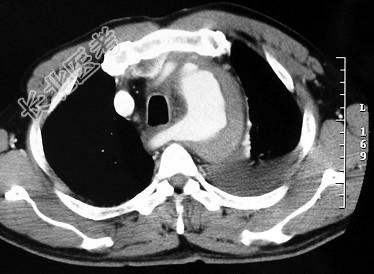

- 单项选择题男,58岁, 有高血压病史,突发胸背剧痛, CT扫描如图,其最可能的诊断为 ( )

A、主动脉瘤

B、主动脉假性动脉瘤

C、主动脉窦瘤破裂

D、高安病

E、主动脉夹层动脉瘤